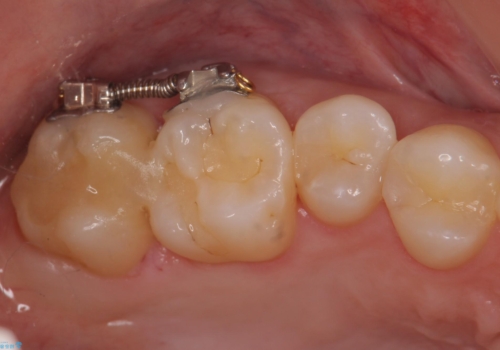

そこで、部分矯正を行い、歯の間を広げてしっかりした歯型を取りました。

広げた期間は2週間ほどです。